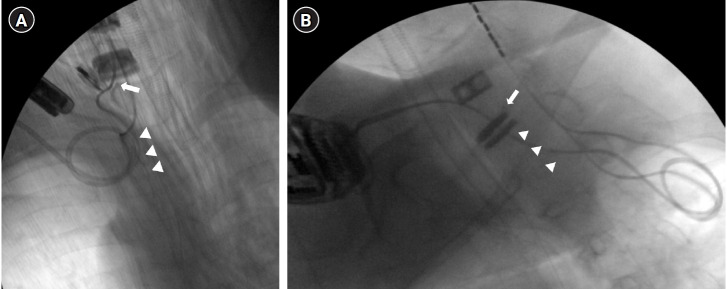

Case: A 64-year-old male patient underwent spinal cord stimulation (SCS) for severe cervical SCI. We proceeded with the ITDD system, placing the catheter tip at the C6 level. After placement of the ITDD system, the patient was monitored for regular refills of morphine sulfate in the drug delivery reservoir every 6 months. We reduced the oral morphine equivalent dose from nearly 333.8 mg/day to 133.8 mg/day.